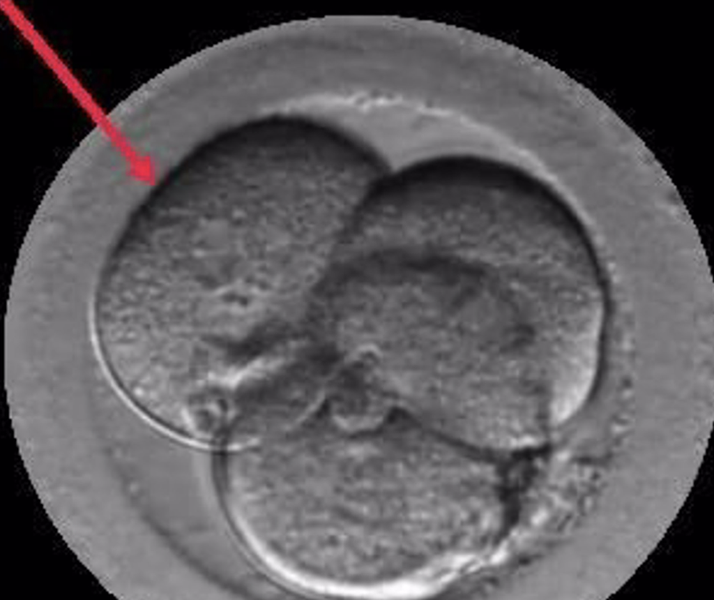

Embrión Multinucleado. - Institut Marquès

El Dr. Borja Marquès es el autor del estudio "Signos de auto-reparación de los embriones en el laboratorio de FIV" cuyas conclusiones apuntan que los embriones poseen un mecanismo de auto-corrección ignorado hasta hoy. Según este trabajo que se presenta esta semana en Murcia, en el 36º Congreso de la Sociedad Española de Ginecología (SEGO), embriones que han sufrido división reversa (desaparición de alguna de sus células) o multinucleación (presencia de dos o más núcleos en alguna de sus células) pueden acabar con éxito, es decir, con un embarazo normal y el nacimiento de un bebé sano.

Gracias a los incubadores con cámaras time-lapse (Embryoscope), en los laboratorios de Institut Marquès ha sido posible captar las imágenes de embriones con división reversa reabsorbiendo sus propias células y de embriones multinucleados expulsando las células anómalas en el 4º o 5º día de vida. Para conseguirlo, se ha analizado el desarrollo de 21.274 embriones, desde su fecundación hasta que llegaron a blastocisto.